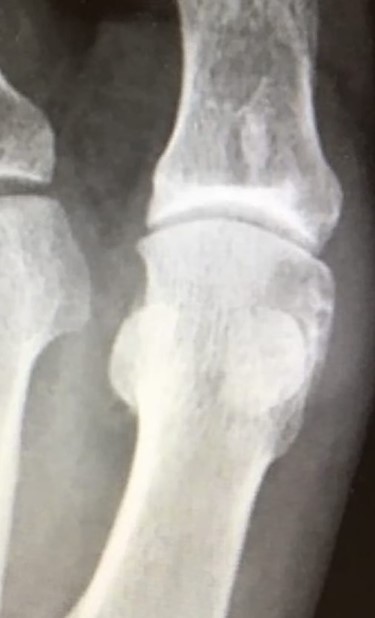

(A + B): (A) Anteroposterior, weight-bearing, X-ray view of the left foot. The red arrow shows a lytic lesion of the subchondral bone, indicating a possible OD lesion on the MH. The black arrow shows the formation of a small, lateral osteophyte. (B) Oblique X-ray view of the left foot. The red arrow shows again radiolucency of the cortical bone as well as small fragmentation of the MH.

Standing anteroposterior (AP), oblique and lateral radiographs of the affected foot were taken. On the AP and oblique views, an OD lesion of the 1st MH was visible (lytic lesion of the subchondral bone and subchondral sclerosis formation) with a lateral-forming osteophyte (Fig. 1A and B). Magnetic resonance imaging (MRI) of the left foot clearly shows the osteochondral defect of the 1st MH (Figs 2 and 3).

Anteroposterior X-ray view of the left foot at 12 months follow-up showing a good-restoring articular cartilage and joint regularity.